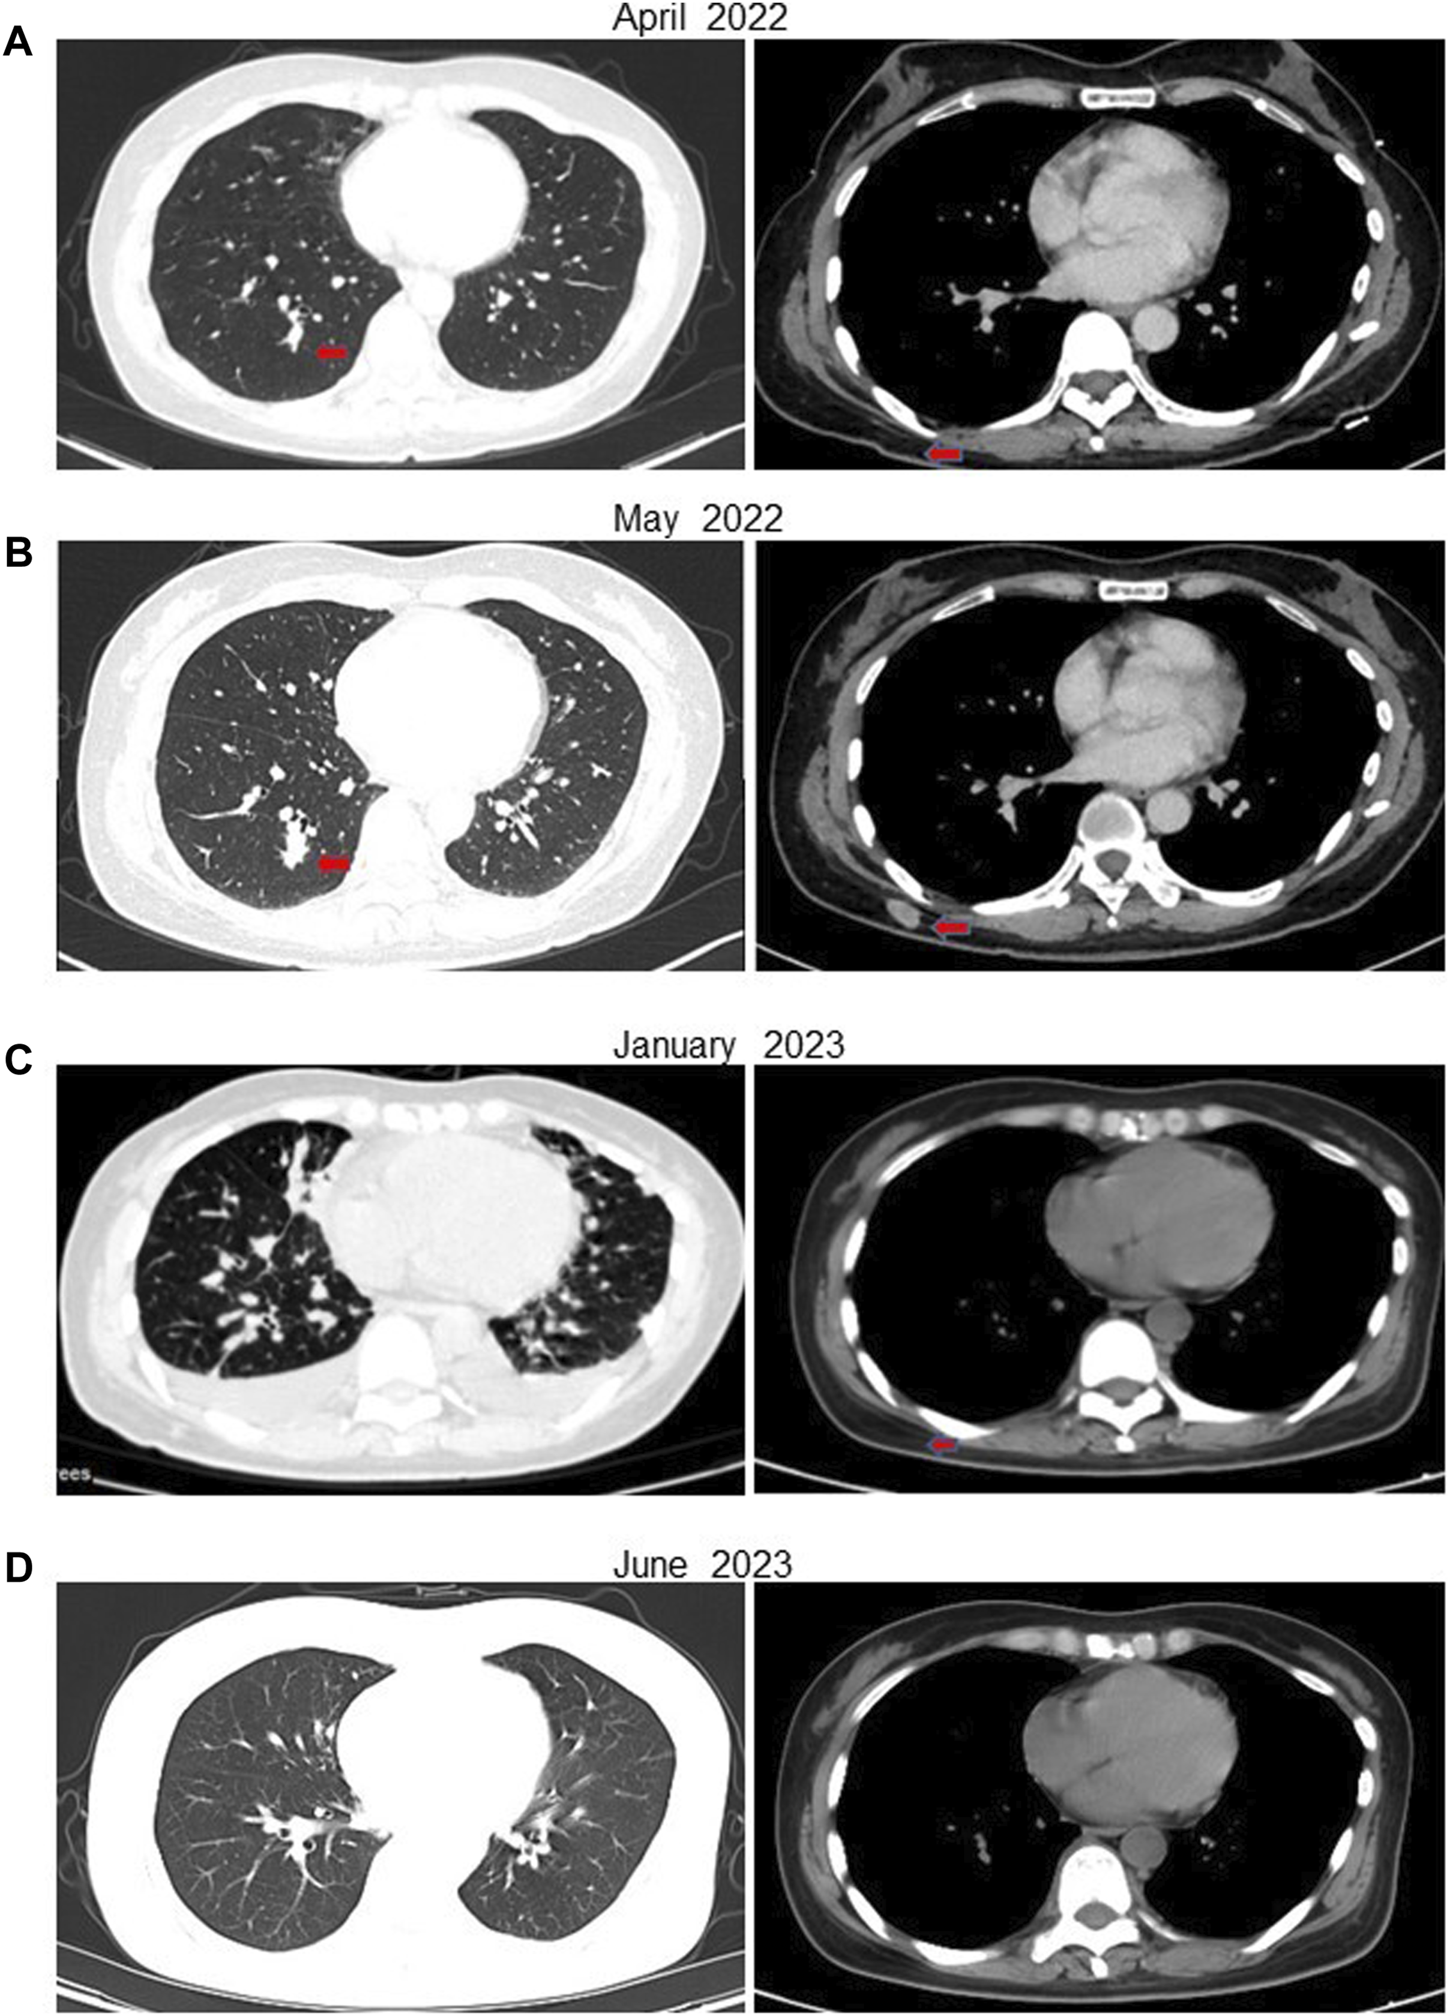

In February 2022, following a diagnosis of high-grade renal cell carcinoma, the patient commenced immediate treatment with two cycles of pembrolizumab combined with sunitinib (Pembrolizumab 200mg, every 3 weeks; sunitinib 50 mg, once daily for 2 weeks, with a 1-week break). Subsequent CT scans in April 2022 revealed significant reductions in the size of subcutaneous nodules and pulmonary metastases on the right back compared to previous scans (Figure 3A). However, due to intolerance to sunitinib, the treatment was modified to pembrolizumab combined with axitinib for 2 weeks (Pembrolizumab 200 mg, every 3 weeks; Axitinib 5mg, twice daily). In May 2022, CT scans indicated an increase in multiple small nodules in various subcutaneous areas and an increase in metastatic tumors in both lungs compared to April 2022 (Figure 3B). Subsequently, the patient underwent treatment with anlotinib in combination with pembrolizumab for eight cycles (Pembrolizumab 200 mg, every 3 weeks; Anlotinib 12 mg, once daily for 2 weeks, with a 1-week break). PET-CT results in October 2022 demonstrated significant progression of bone metastases throughout the body compared to May 2022 (Supplementary Figure S1A). In December 2022, the patient received treatment with pembrolizumab alongside oral ST1898 targeted therapy. However, a CT scan in January 2023 revealed significant enlargement of bilateral lung metastases compared to October 2022 (Figure 3C). Subsequently, in February 2023, following the diagnosis of FH-deficient renal cell carcinoma, the patient’s treatment regimen was adjusted. Treatment with pembrolizumab, erlotinib, and bevacizumab was initiated, although immunization was temporarily suspended due to significantly increased pituitary prolactin levels. In March 2023, the patient underwent eight cycles of treatment with bevacizumab and erlotinib. A CT reexamination in June 2023 showed a significant reduction in metastatic lesions, with the patient’s condition stabilized (Figure 3D). The timeline of the case is illustrated in Figure 4, with the top axis depicting the diagnostic process and the bottom axis showing the treatment process. Consent for publication of this case report was obtained from the patient.

FIGURE 3

CT of the patient at various stages after receiving treatment. (A) In April 2022, after 6 weeks of treatment with pembrolizumab in combination with sunitinib, the patient’s metastases were significantly reduced. (B) In May 2022, after 5 weeks of treatment with pembrolizumab in combination with axitinib due to the patient’s intolerance of sunitinib, the subcutaneous nodule on the right side of the back was enlarged compared with the previous one. (C) After eight cycles of the original regimen, a CT in January 2023 showed multiple metastases in both lungs that were significantly more advanced than before. (D) ACT in July 2023 showed a significant reduction in the patient’s metastatic lesions.